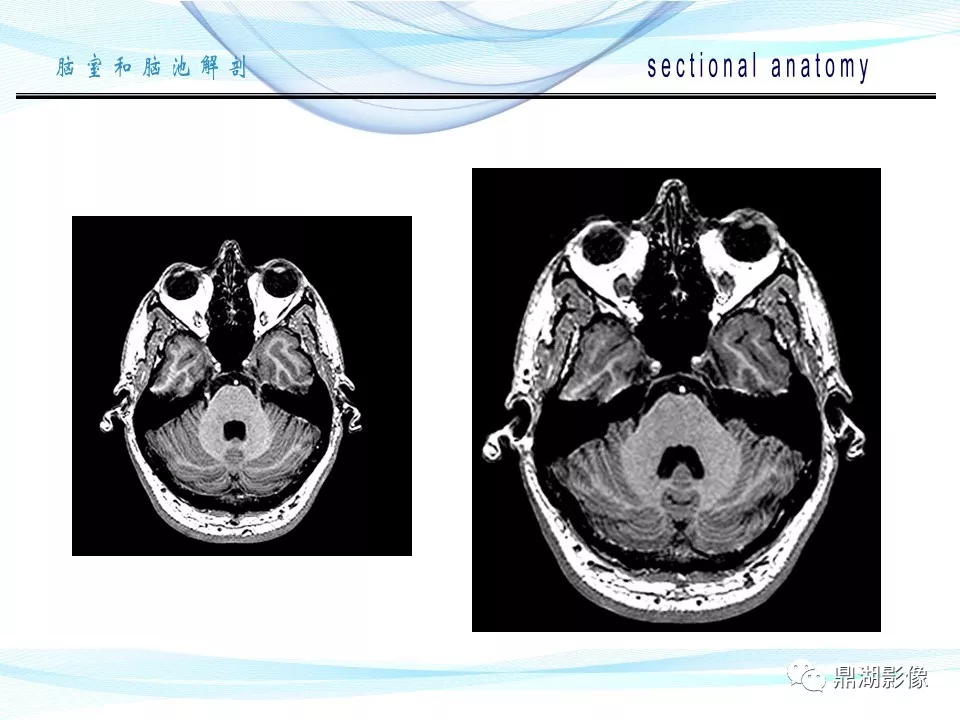

必点收藏 | 脑池和脑室断层解剖

超全详解:脑池和脑室断层解剖